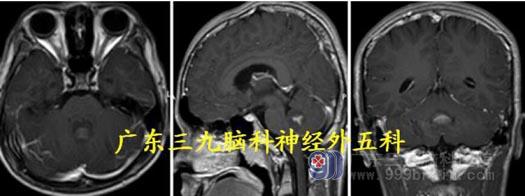

头颅MR:小脑蚓部示一囊实性占位性病变,并示多发分隔影,增强后实性部分呈囊壁呈明显异常强化影,大小约为6.4cm×5.9cm×5.6cm,小脑蚓部占位性病变,考虑为毛细胞星形细胞瘤可能;小脑扁桃体下疝;幕上梗阻性脑积水。